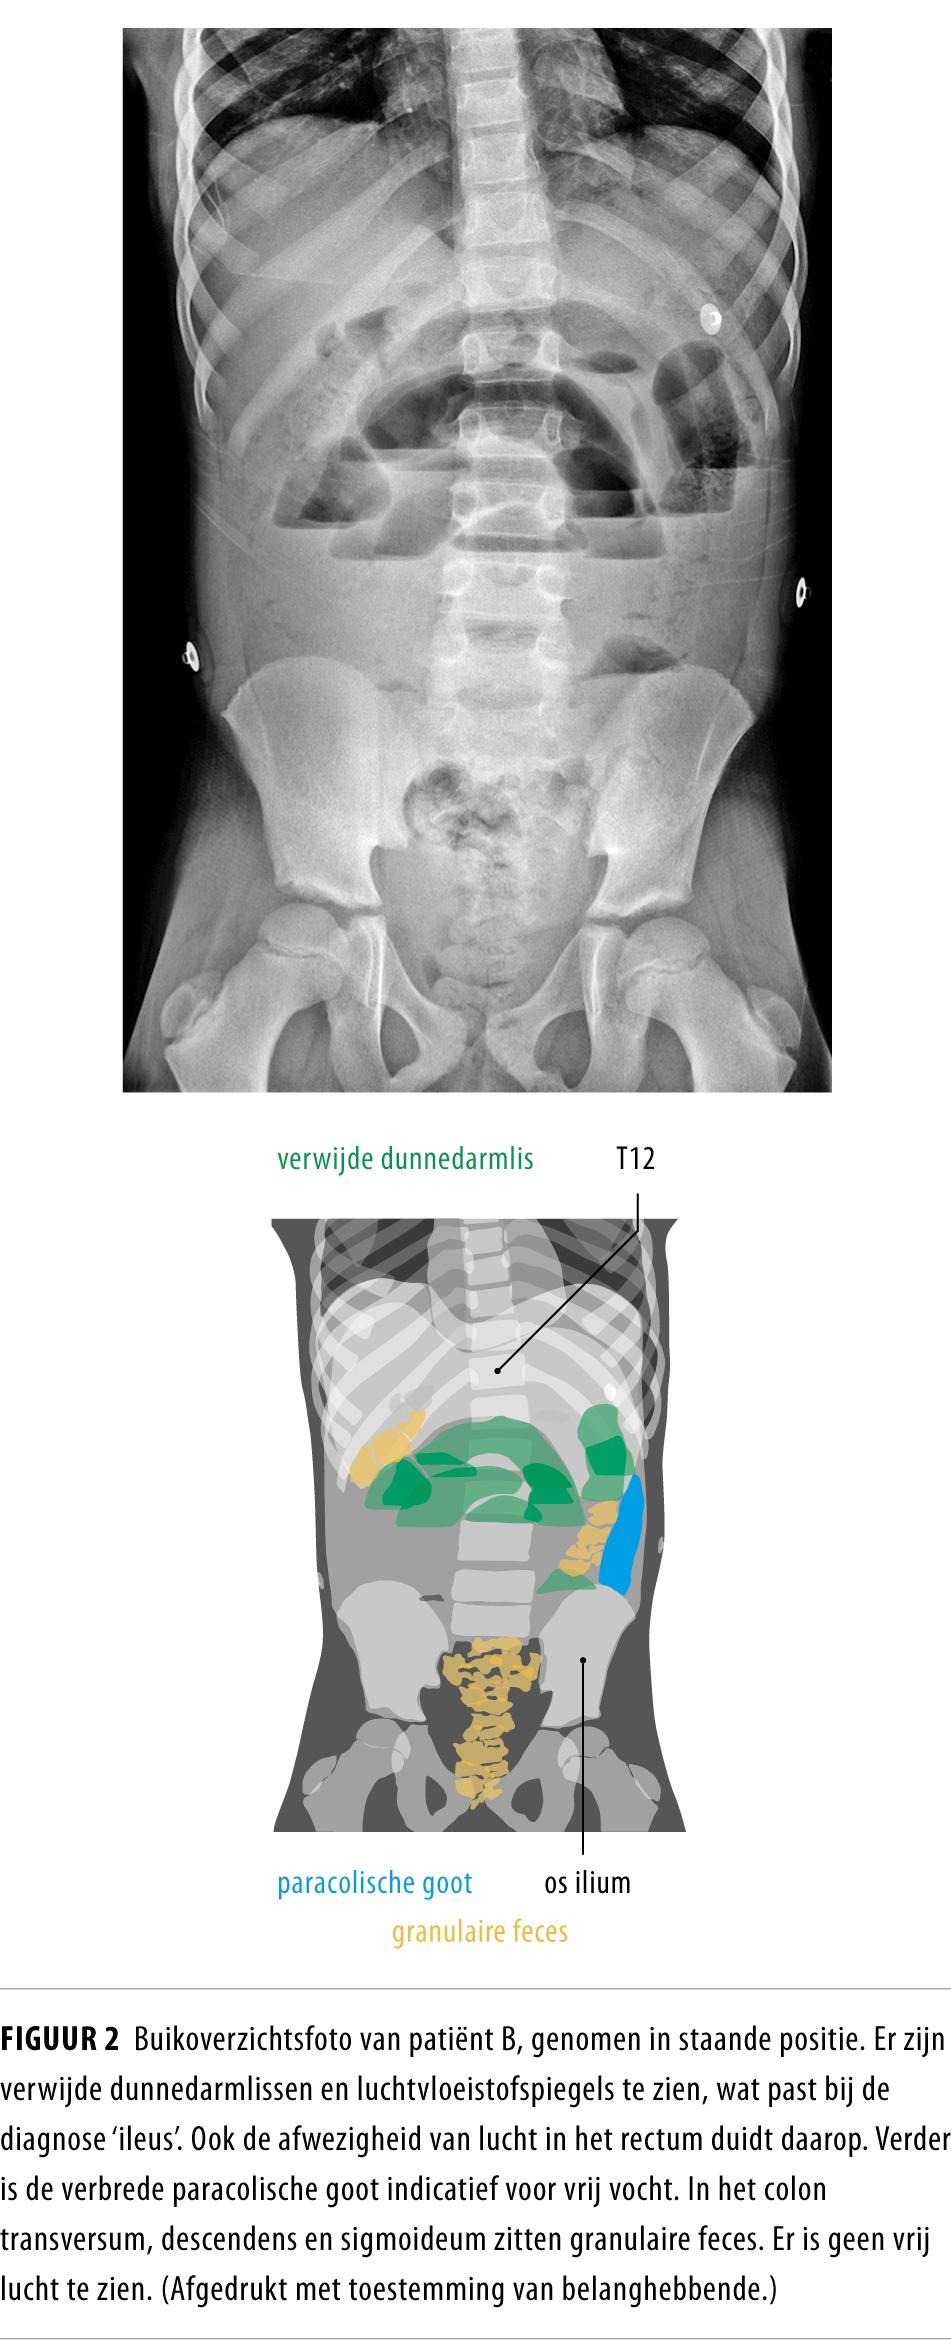

Ileus op basis van een beklemde liesbreuk of invaginatie is algemeen bekend bij kinderen in de eerste levensjaren. Mechanische ileus bij oudere kinderen die nooit in de buik zijn geopereerd is daarentegen een relatief onbekend fenomeen. Bij deze kinderen zijn de anamnese, het lichamelijk onderzoek en de laboratoriumuitslagen vaak aspecifiek, terwijl vroege herkenning essentieel is voor een goede uitkomst Dit illustreren we aan de hand van 2 patiënten die beiden mechanische ileus hadden op basis van een aangeboren afwijking.